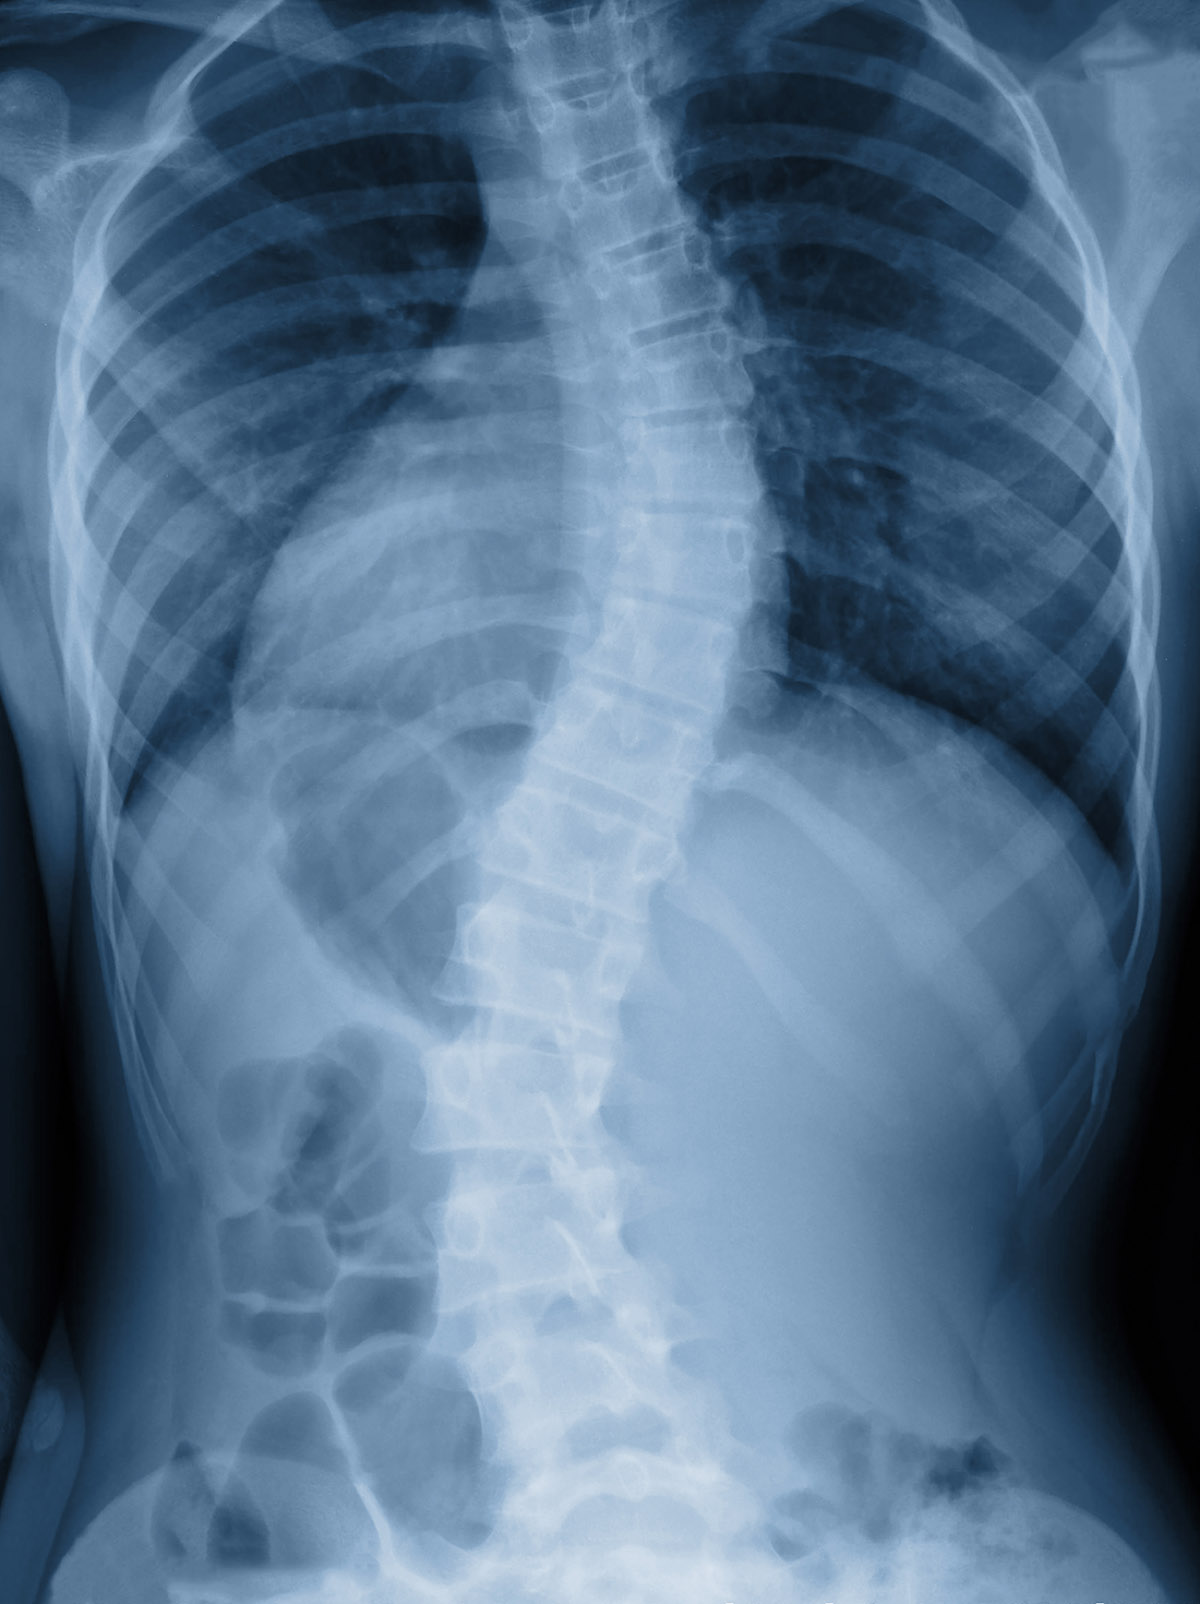

H σκολίωση είναι ένα μυοσκελετικό πρόβλημα συνυφασμένο στο μυαλό των περισσότερων με την παιδική και εφηβική ηλικία. Πρόκειται για μια πλάγια απόκλιση της σπονδυλικής στήλης, μεγαλύτερη από τις 10 μοίρες, με ταυτόχρονη στροφή των σπονδύλων. Συνήθως η μία πλευρά είναι πιο εξογκωμένη από την άλλη, ενώ παρατηρούνται ασυμμετρίες στους ώμους και τη λεκάνη κατά την κλινική εξέταση.